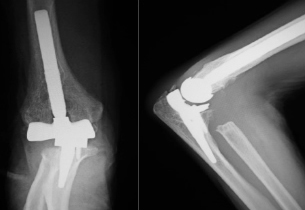

関節リウマチ

リウマチによる手・肘の変形に対する治療は一般的に難易度が高く、また習熟している施設は限られています。当院ではリウマチ手指や肘に対する人工関節手術を積極的に行い、良好な治療成績を得ています。また比較的若年の方で関節面が保たれている場合は可能な限り関節温存手術を行います。当院の担当医はリウマチ指の人工関節手術、人工肘関節手術、人工関節を用いない手指軟部組織形成術や肘関節形成術の経験も豊富です。人工関節は複数の種類がありますが、患者さんの状態に合わせて使い分けています。肩については、変形性関節症のところでも触れている、近年開発された肩の特殊な人工関節(リバース型)が導入されて以降、良好な成績が得られています。